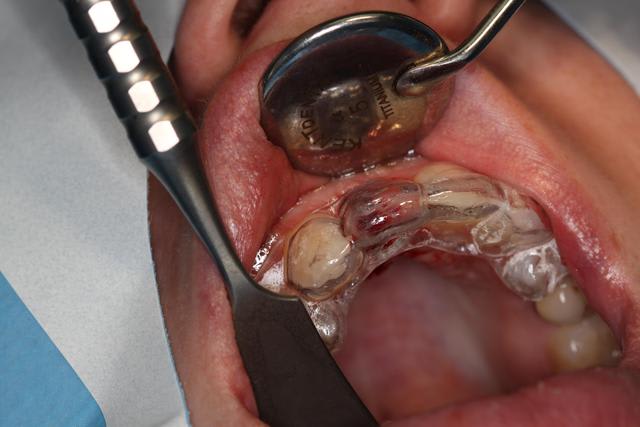

Implant posé ce matin

Le guide n'a pas été utilisé. Pas assez stable, délicat pour la visibilité, me sentais moins bien avec que sans : l'axe me paraissait pas correspondre, peur de fraiser de la résine.

Extraction simple, hauteur racine 10mm.

Alvéole propre, "boulevard" pour implanter.

Premier forage légerement en palatin, trop car petite excursion dans canal retro incisif.

Reprise de l'axe finalement au fond de l'alvéole.

Implant Legacy (ayé) 3 4,2x16mm

Bonne stabilité primaire, saignement abondant.

Utilisation pilier provisoire résine plateforme 4.7, injection de flow et polissage pour galber mais pas trop pour que la gencive revienne.

Pas de sutures, pas besoin.

Les critiques (productives et modérées) sont les bienvenues